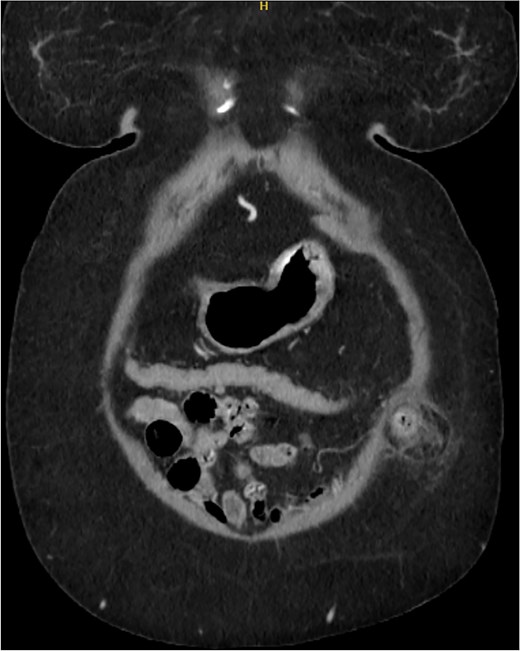

Postoperatively, the patient had an uneventful course and was discharged on Day 5. At the 6-month follow-up, she remained asymptomatic. A CT scan performed at her request for reassurance showed no signs of recurrence or acute abdominal pathology (Figs 4 and 5).

Sagittal section of CT abdomen and pelvis 6 months after the surgery.